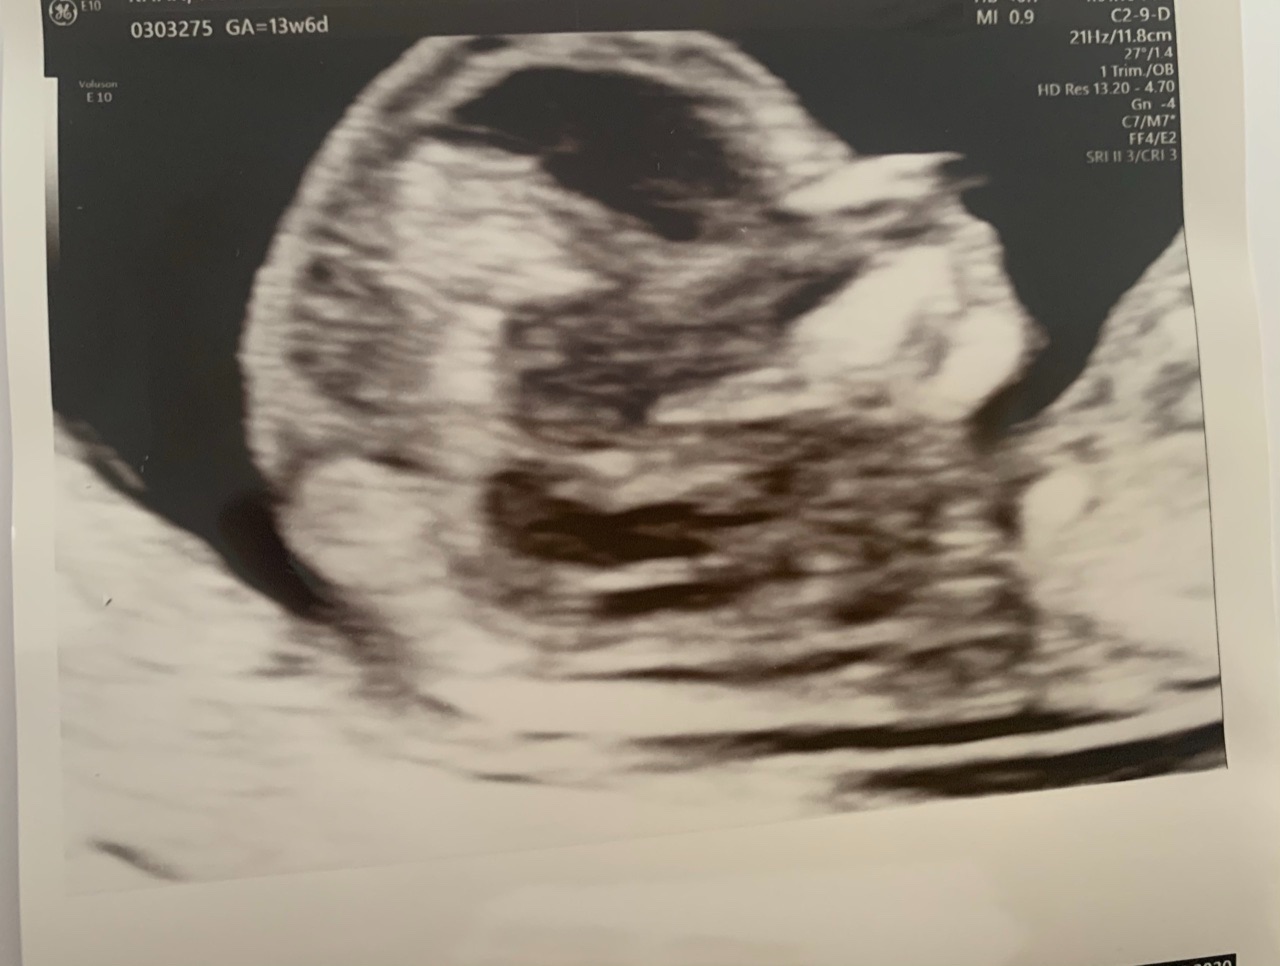

can i have a look at your ultrasound please at first

Dr Aqsa please see the ultrasound pics below

Please check now

Dr Nazish Ali please see the ultrasound reports

Doctors, please see the ultrasound pics below

dear yes because these are markers for chromosomal abnormalities usually we do NT for screening